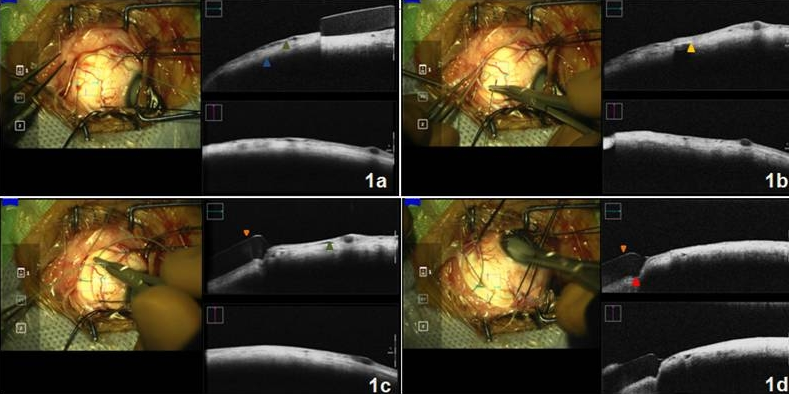

A 10-year-old male presented with diminution of vision in his right eye (OD) for the past 5 months. Examination revealed a white cataract with no view of the fundus. Total retinal detachment was detected on ocular ultrasonography. Pars plana lensectomy (PPL) with pars plana vitrectomy (PPV) along with an encircling 240 scleral band was planned. After performing a 3600 conjunctival peritomy and bridling of all the recti with 3-0 silk suture, a 240 encircling element (Labtician Ophthalmics, Oakville, Canada) was passed underneath all the recti muscles. This was followed by passage of 5-0 dacron (polyethylene terephthalate) sutures (Aurolab, Madurai), 12mm from the limbus in all quadrants, to secure the encircling 240 band. Mi-OCT (The RESCAN 700, Carl Zeiss Meditec, Germany) was switched on while passing the needle through the sclera to assess the depth of the suture bite. Mi-OCT was also used to assess the amount of scleral indentation achieved after the mattress sutures were tied. Figure 1a [Fig. 1] shows the presence of a hyporeflective space (green arrowhead), which corresponds to the passage of suture through the sclera. This helps the surgeon assess and titrate the desired depth of the suture through the sclera. Full-thickness of sclera and sclera-choroidal interface (blue arrowhead) was well appreciated using intraoperative OCT. Figure 1b [Fig. 1] shows a hyperreflective band (yellow arrow head) with back shadowing which corresponds to the real-time passage of the needle through the sclera. Figure 1c [Fig. 1] shows a hyporeflective band (orange arrowhead) which corresponds to the encircling 240 scleral band. Passage of suture can be appreciated as hyporeflective space in the sclera (green arrowhead). Similarly mattress sutures were passed in all four quadrants. The desired scleral indentation (red arrowhead) was achieved by tying the scleral sutures (Figure 1d [Fig. 1]).

Figure 1: a) Realtime passage of suture through the sclera, seen as hyporeflective space (green arrowhead). Sclero-choroidal junction can be easily appreciated on Mi-OCT (blue arrowhead). b) Hyperreflective band with backshadowing (yellow arrowhead) corresponding to real time passage of suture needle. c) Encircling 240 band (orange arrowhead) and hyporeflective space corresponding to depth of suture tract (green arrowhead). d) Desired scleral intend (red arrowhead) achieved by tying the scleral sutures.